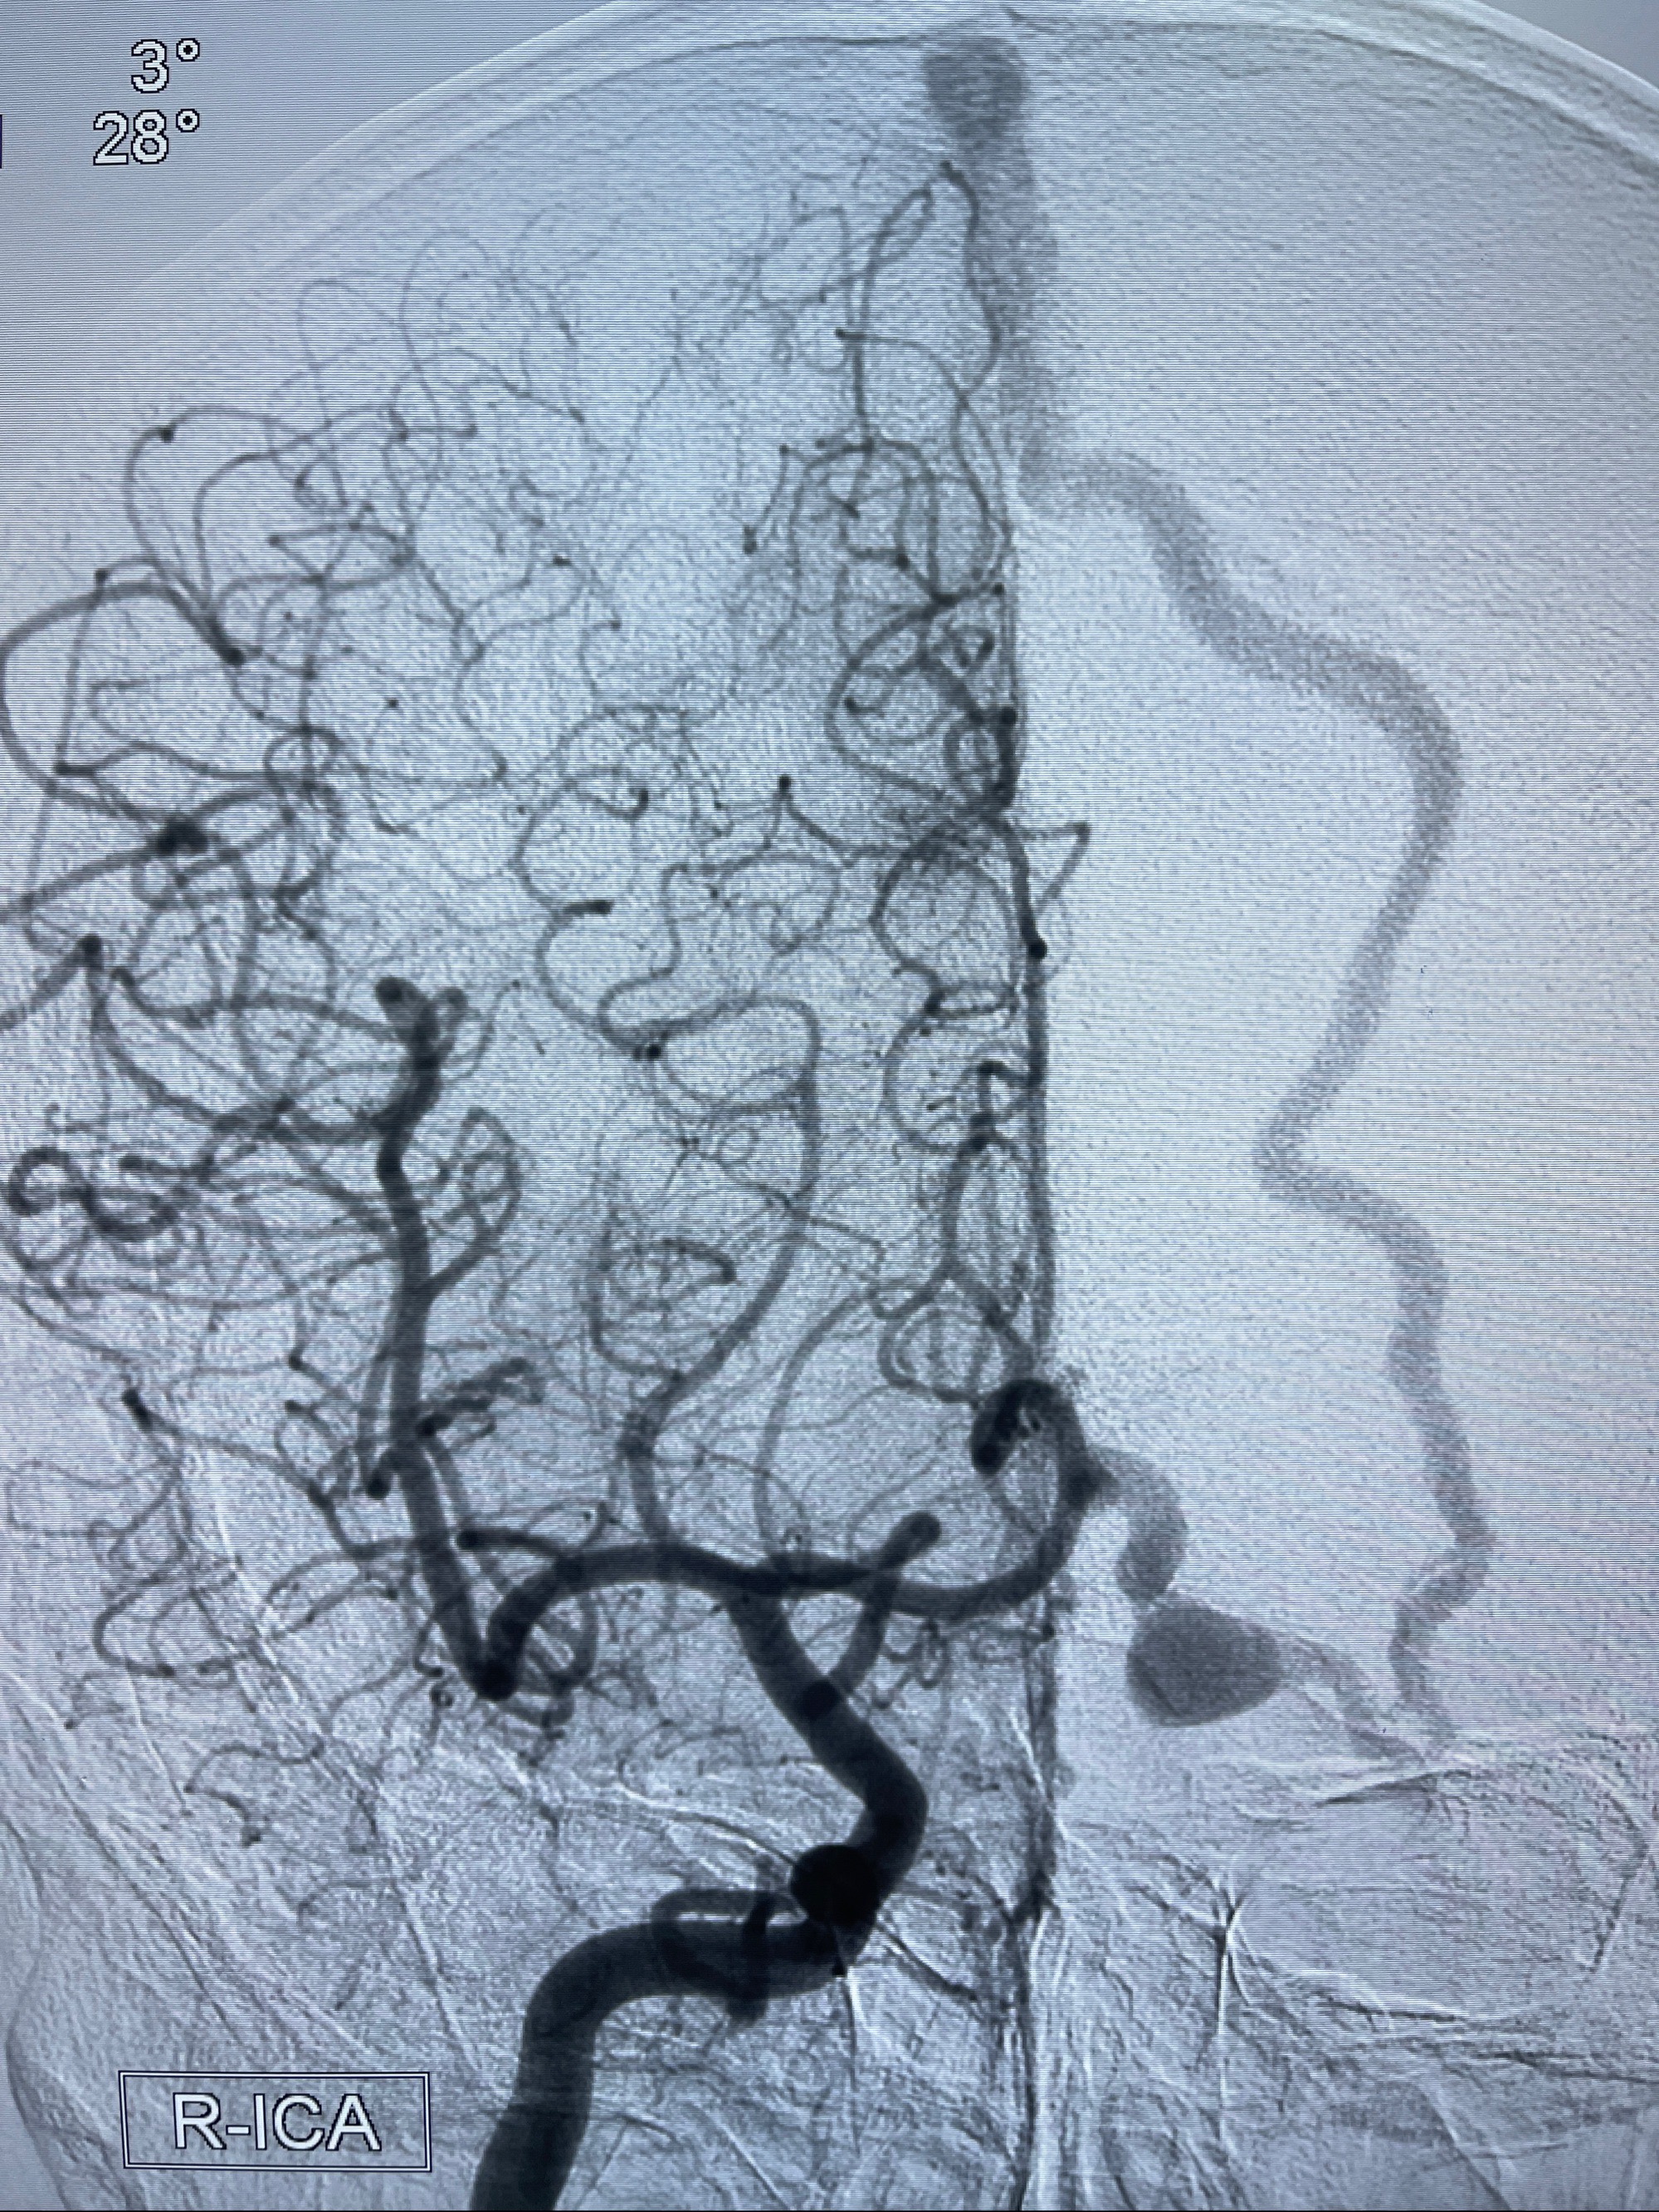

2023年8月21日]景德镇市第一人民医院脑血管造影检查,提示:主动脉弓、双侧颈总动脉、锁骨下动脉造影未见异常,左侧大脑前动脉静脉瘘。

2023-09-13全脑血管造影:前颅底硬脑膜动静脉瘘,供血动脉为双侧胼周动脉、眼动脉脑膜支,静脉向上矢状窦方向引流

- 介入干预:静脉途径栓塞or动脉途径填塞?